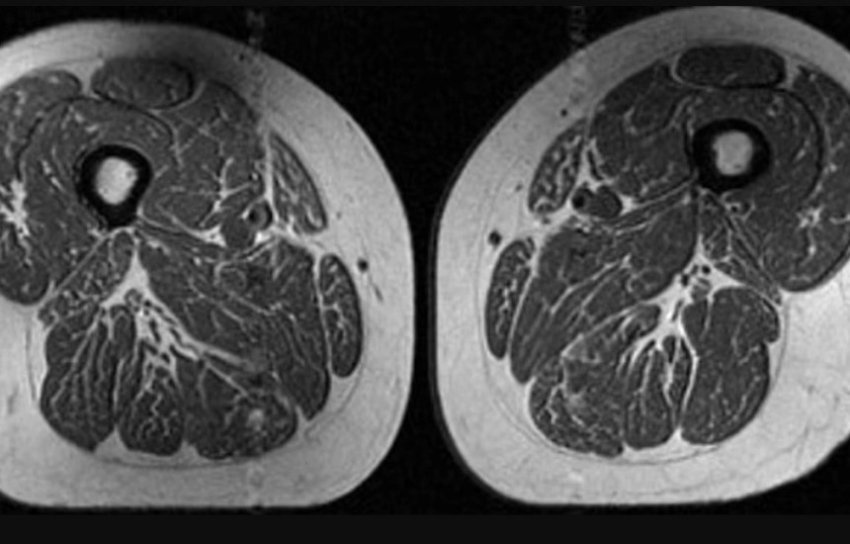

Imazhet nga rezonanca magnetike (MRI) që tregojnë kofshën e një gruaje 62-vjeçare që merrte rreth 87 për qind të kalorive nga ushqime shumë të përpunuara

Një imazh nga rezonanca magnetike (MRI) tregoi kofshën e një gruaje 62-vjeçare që merrte rreth 87 për qind të kalorive nga ushqime shumë të përpunuara. Në vend të muskujve të fortë, skanimi zbuloi shtresa të shumta yndyre të shpërndara brenda dhe midis fibrave muskulore, ka shkruar CNN.

Sipas studimit të ri, prania e yndyrës brenda muskujve është një sinjal për probleme serioze shëndetësore, sidomos te personat që janë në rrezik për osteoarthritis të gjurit.

“Është shqetësuese sidomos sepse këta individë, të skanuar në një kohë kur nuk kishin ende shenja të osteoartritit, tashmë tregonin cilësi të dobët të muskujve”, ka shtuar Akkaya.

Lidhja mes yndyrës në muskuj dhe dhimbjes së gjurit është e fortë. Yndyra pengon rigjenerimin e fibrave muskulore dhe i dobëson ato, duke rritur rrezikun për osteoarthritis, forma më e zakonshme e sëmundjeve të nyjave që prek rreth 375 milionë njerëz në botë.

Rezultatet kanë treguar qartë se sa më shumë ushqime tё shumë përpunuara të konsumonte një person, aq më shumë yndyrë kishte në muskujt e kofshës, pavarësisht sasisë së kalorive.